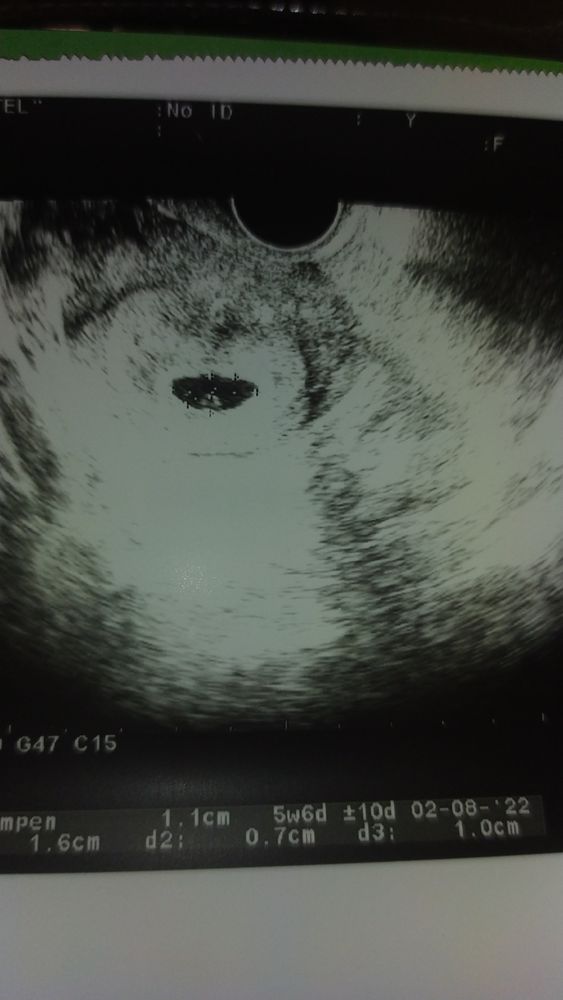

Срок акушерский 6,1 неделя, ПЯ 21ММ мешочек 3мм.

Эмбрион и СБ не видела врач УЗИ

Фото прикрепила... У кого так было? Как закончилось? Успокойте меня...

Светлана Сопчинская, Делала 4 дня назад - посмотрите выше фото УЗИ - был 11мм ПЯ и четко визуально видно МЕШОЧЕК и эмбриончик...

Азиза Себединова, вот у меня в 6.2 узи : ПЯ - 21 мм КТР - 5.1 мм ЖМ - 2.5 мм СБ - ЧСС 122. смотрели вагинально. Так что через недельку идите к другому специалисту как минимум